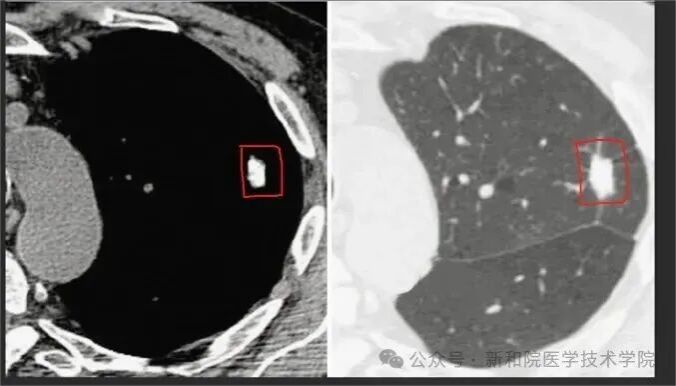

2号嫌疑人:【钙化灶】—— 肺部的“疤痕勋章”

【侦探描述】 CT上的高密度亮点,白得发亮,密度和骨骼接近。

【身份揭秘】 这通常是肺部的一枚“良民证”。

90%以上是良性: 多是既往得过肺结核、肺炎,身体打赢了胜仗,愈合后钙盐沉积形成的“陈年旧疤”。